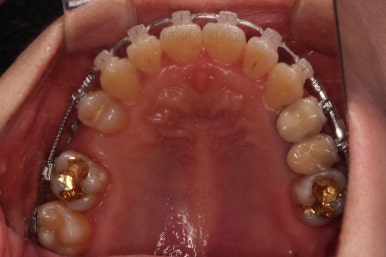

임플란트 보철이 깔끔하게 들어갔고, 교정치료도 마무리가 되었습니다.

화살표 부분은 임플란트가 안들어갔는데요.

약간의 우여곡절이 있긴했었지만 엄밀히 따지면 위아래가 지그재그로 껴들어가는 교합의 특성상 윗니는 1개 모자라도 교합에는 크게 문제가 없답니다.

해당 부분을 임플란트를 해주면 좋겠지만 환자분도 충분히 고민 후에 원하실 때 식립을 하기로 마무리르 하였습니다.

부산연산동치과 전후 사진을 비교해 보겠습니다.

총 22개월 걸렸고, 임플란트는 1개로 마무리를 했습니다.